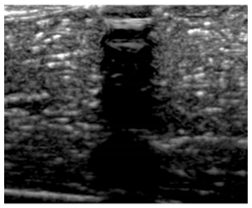

Figure 3.

(a) Selection of ROI-1 and ROI-2 in the B-mode image of the muscle without implants. (b) Selection of ROI-3 and ROI-4 in the B-mode image with aerogel implants.